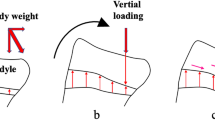

The rotation angle of the femur significantly correlated with the spherical condylar angle during 20°–120° of knee flexion. The spherical condylar angle is the angle between the GCA and PCA that is tangent to the tibial articular surface. If the GCA is the approximate flexion–extension axis of the knee joint during mid-flexion to deep flexion, GCA is the axle connecting two differently sized spheres of the medial and lateral posterior condyles of the femur, and PCA is the ground. Regarding the rolling motion of the femur relative to the tibia excluding sliding and slipping motion of the femur, the rotation angle of the femur per the same flexion angle depends on the size of medial and lateral approximate spheres during medial pivot motion (Fig. 8). The spherical condylar angle is influenced by these sizes, and thus exhibited a correlation with the femoral rotation angle. However, the rotation angle of the femur did not correlate with the ratio of the posterior condyle radii. In addition to the size of the posterior condyles, the spherical condylar angle is influenced by the distance between the center of approximate sphere of medial and lateral posterior condyles. On the other hand, the ratio of the posterior condyle radii is influenced only by the posterior condyle sizes. In other words, the radii ratio does not directly affect the GCA, which is the approximate flexion–extension axis. Therefore, the ratio of the posterior condyle radii did not correlate with the rotation angle of the femur. Hoshino et al. performed in vivo motion analysis to evaluate knee kinematics during downhill running on a treadmill using a 3D to 2D image registration technique. They showed that the internal tibial rotation positively correlated with the condylar twist angle, although they defined the condylar twist angle as the angle between the trans-epicondylar angle and transcondylar angle, which is the same as the GCA [22]. Thus, they found that the morphological characteristics of the femoral condyle, which were associated with the approximated flexion–extension axis, affected the tibiofemoral rotation. The correlation between the rotation angle of the femur and the flexion–extension axis of the knee was also demonstrated in our study, although the analyzed motions were different in the two studies.

Relationship between spherical condylar angle and rotation angle. a The Spherical condylar angle can be likened to the angle between the axle and the ground. If the changed in knee flexion angle is the same, b) rotation angle is small when the approximate sphere of lateral posterior condyle is small. C rotation angle is large when the approximate sphere of medial posterior condyle is big

Furthermore, the inclination angle of the medial posterior condyles was correlated with the rotation angle of the femur relative to the tibia throughout 20°–120° of knee flexion in this study. When the medial posterior condyle tilted medially (in the same direction as the lateral posterior condyle), the external rotation angle of the femur was increased. If the fulcrum of the pivot motion, the medial posterior condyle, has an opposite tilt relative to the lateral posterior condyle, it may create an antagonistic force to the lateral posterior condyle moving medially (i.e., externally) during knee flexion. Conversely, it was thought that if the medial posterior condyle had the same directional inclination as the lateral posterior condyle, the medial translation (i.e., externally rotation) of the lateral posterior condyle could be induced smoothly (Fig. 10).

The relationship between the tilt of posterior condyle and the rotation of the femur. A When both the medial and lateral posterior condyles are tilted medially, a medially directed force is produced during knee flexion, resulting in external rotation of the femur. B When the medial posterior condyle is tilted laterally, the forces generated by the tilt of medial and lateral posterior condyles are cancelled out